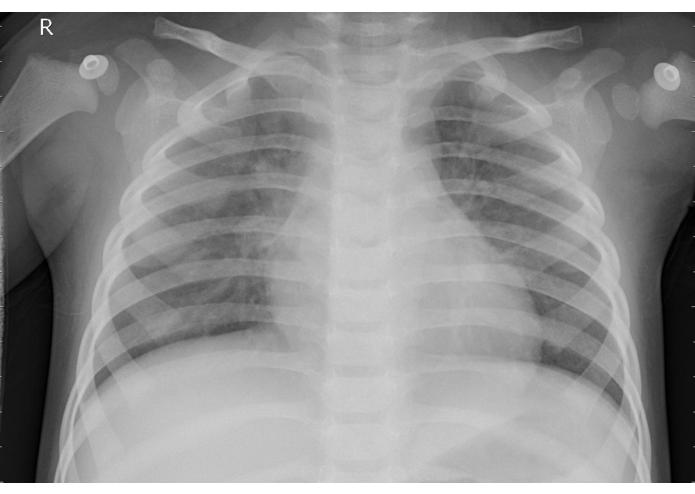

Machine Learning for Medicine - Pneumonia nowadays is still a life-threatening disease that may affect young children's lives. To exam the illness, an X-ray scan is usually taken and the infected area may be detected by doctors. The project aims to develop a program that assists doctors to determine the situation.

Image Classification - X-ray images are processed and input into the program and an output stating whether there is a case of pneumonia will show.